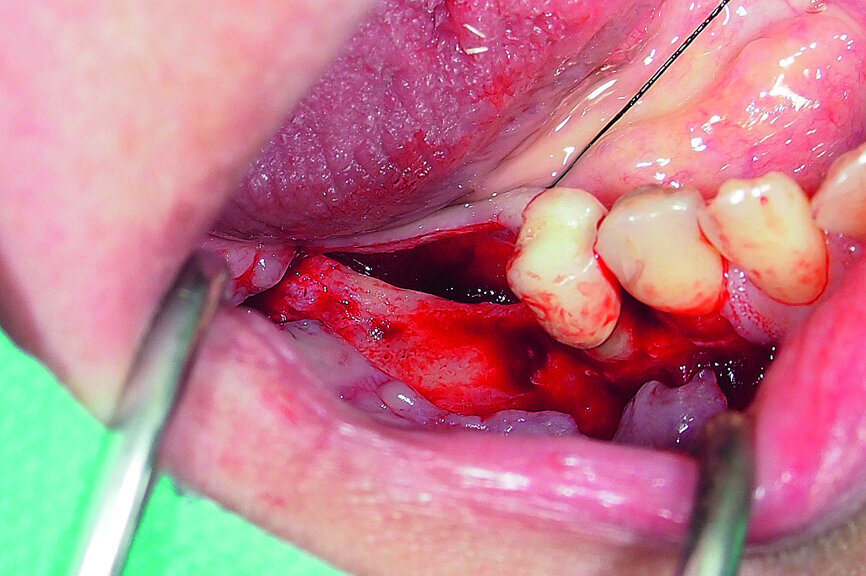

Fig. 17: Creation of space in between the buccal and lingual lamina with the intact attached periosteum on the buccal.

A demonstration of this technique is shown in Figures 13 to 20. This case presents an elderly woman who had lost her teeth in the lateral mandible decades ago. Being a healthy non-smoker with good oral hygiene, no history of periodontal disease and low masticatory forces, she was an adequate candidate for bone grafting together with implant placement. The future restorative margins allowed the usage of ridge splitting (Figs. 13 & 14). Therefore, we opted for a ridge split with vertical releases carried out utilising a partial-thickness flap. The periosteum was left attached in order not to impede the perfusion of the buccal plate (Fig. 15). After ridge splitting, the buccal and lingual plates were separated with the use of bone spreaders (Split-Control Plus, Meisinger) to allow the placement of two GC Aadva Standard implants, one of 3.3 mm in diameter and 8.0 mm in length and the other measuring 4.0 mm in diameter and 8.0 mm in length (Figs. 16–18).